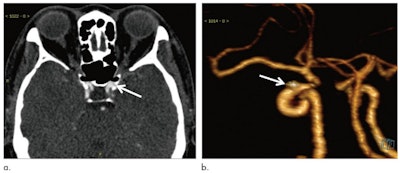

However, the authors also flagged study limitations, such as the retrospective design and false positives "in areas with bony structures, veins, and vascular bifurcations and curvatures and calcified plaques." They are working to improve the algorithm.